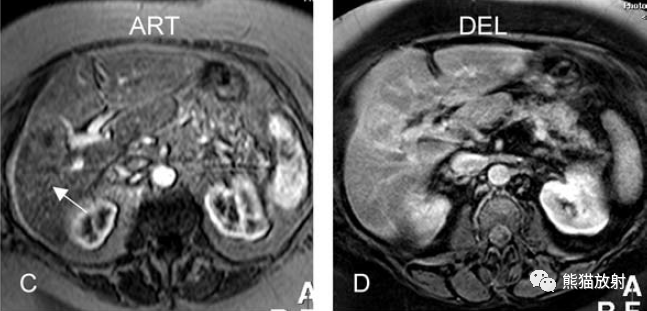

增強動脈期(ART):不均質強化;

延遲期(DEL):部分廓清,部分持續強化。

膽囊癌。A~D圖:上方層面,表現如上所述,形成腫物侵及肝臟。E、F圖:下方層面示膽囊壁不規則增厚,明顯不均質強化。